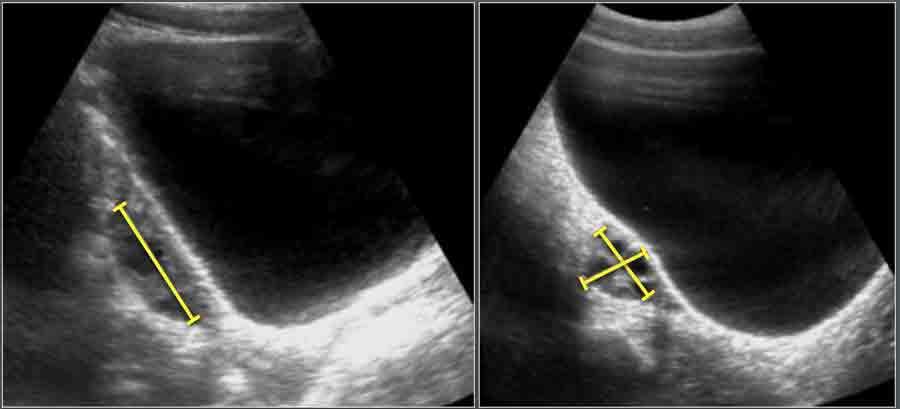

Ống Mật Chủ

Vật liệu và Phương pháp

Tổng cộng 173 bệnh nhi liên tiếp (100 bé trai và 73 bé gái) được chỉ định siêu âm bụng vì lý do không liên quan đến bệnh lý gan mật đã được đưa vào nghiên cứu. Độ tuổi dao động từ 1 ngày đến 13 tuổi (trung vị 5,0 tuổi).

Ở tất cả các đối tượng, đường kính ống mật chủ đo được ≤ 3,3 mm.

Hình ảnh

Hình ảnh siêu âm cắt ngang ống mật chủ và các cấu trúc giải phẫu xung quanh.